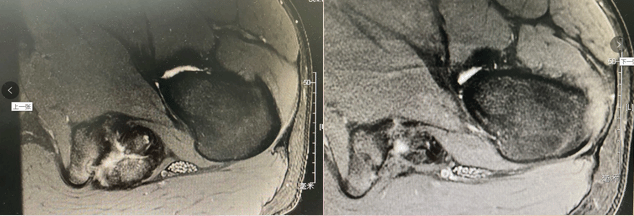

国际首创关节镜下软骨钉植入治疗髋臼软骨剥脱损伤,目前髋组已完成数十例髋关节镜下软骨剥脱修复术,在手术指征的选择,手术技术,围手术期管理等方面有较为先进的经验,处于国内领先,国际一流地位。